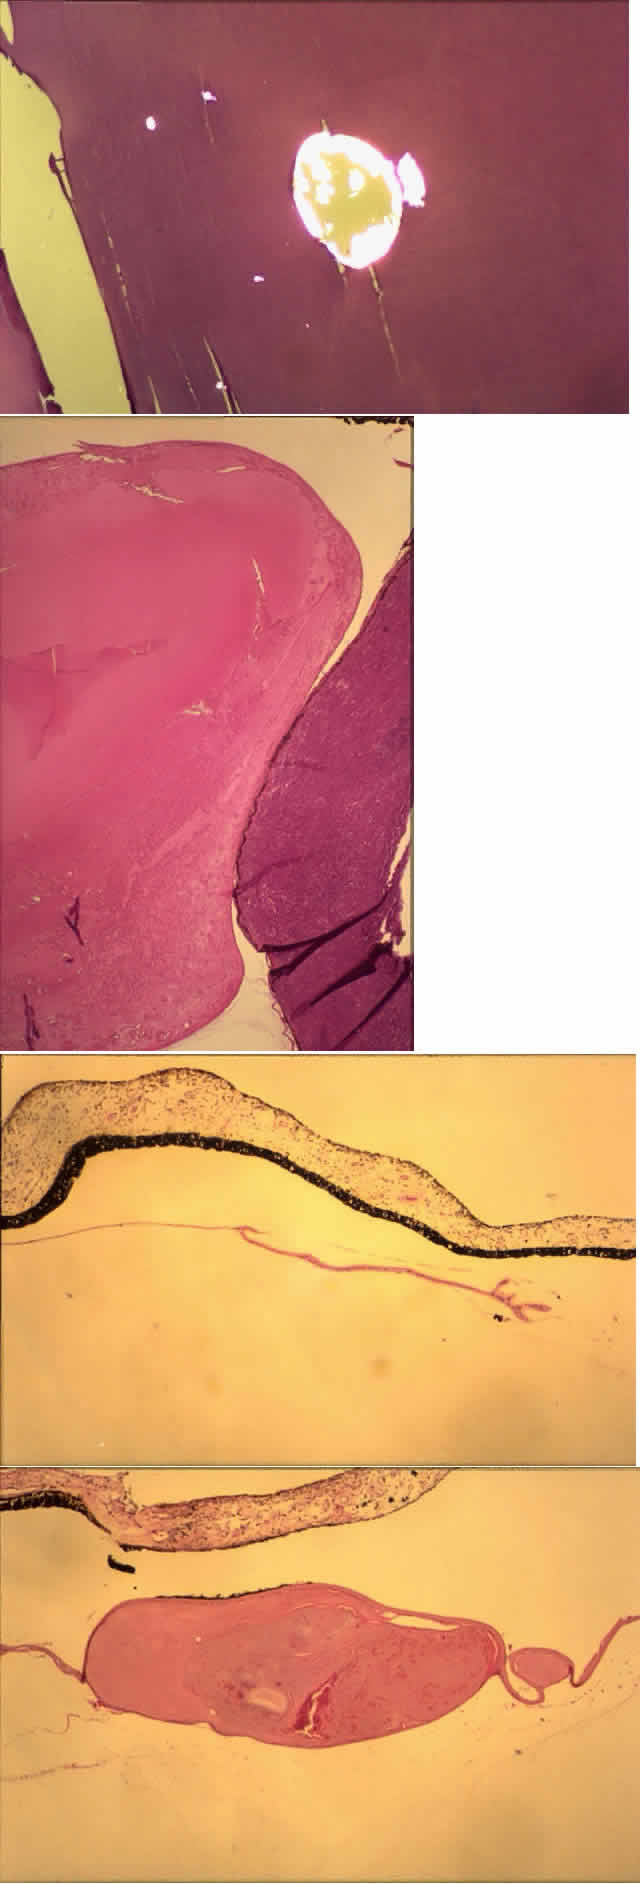

Histologic examination shows an unequal splitting of the anterior capsule (Fig. 1). Electron microscopic examination shows that the lens capsule is laminated and the anterior layer or layers are split free.29 The free portion is quite thin, and it can be rolled or folded over.27

Fig. 1. True exfoliation of the lens capsule. The anterior lens capsule is split and floats away from the rest of the lens (arrow). The subepithelial disruption is artifact. (H & E, magnification × 234; Courtesy of Dr. W.R. Green, Baltimore, MD)

Clinically, in its classic manifestation, pseudoexfoliation syndrome is manifest as a whitish, fluffy deposit on the lens surface and at the pupillary margin. Typically there is a circular clear zone in the midperiphery of the lens, where the iris comes in contact with it (Fig. 2). This syndrome is important to recognize because a type of secondary open-angle glaucoma that can be difficult to control is associated with pseudoexfoliation in more than 20% of eyes.31 Other associated changes include poor dilatation of the iris, melanin dispersion from degeneration of the iris pigment epithelium, and iris stromal atrophy, which are visible clinically as transillumination defects.32

Fig. 2. Pseudoexfoliation syndrome. A and B. Central disc surrounded by a relatively clear zone, surrounded in turn by a peripheral granular area. C. Scanning electron micrograph shows relatively clear zone (Z) surrounded by the central edge of the peripheral granular area. (B, courtesy of Dr. G. Naumann, SEI 73-985; C, courtesy of Dr. R.D. Eagle, Jr;) magnification × 900)

Histologic examination shows exfoliation deposits appearing as short strands of eosinophilic material, which are found on the surface of the lens and zonules and within and adjacent to the ciliary body and iris (Color Plate 1A). On electron microscopic examination, these strands are found to be thick, straight, and densely osmiophilic, with associated thin microfibrils.33

COLOR PLATE 1 A. Pseudoexfoliation fibers on the lens capsule. The dark areas are pigment aggregates (PAS, magnification × 146) B. Anterior polar cataract. The lens epithelium has undergone fibrous metaplasia, and the anterior capsule is wrinkled. A nwe anterior capsule has formed with subjacent normal lens epithelium (PAS, × 58). C. Posterior subcapsular cataract with large bladder cells (H & E, × 58). D. The cortex is liquefied and granular, with more solid-appearing nuclear fragments (H & E, × 58).

Subcapsular cataracts are caused by proliferation of the lens epithelium. Normally a monolayer, the epithelial cells, when stimulated to proliferate, also undergo fibrous metaplasia and generate an irregular fibrous plaque with wrinkling of the lens capsule. The individual cells, however, still secrete basement membrane. On histologic examination, each cell is surrounded by basement membrane material. A new anterior capsule may be secreted, under which is a new layer of lens epithelium (Figs. 3 and 4; Color Plate 1B).

Fig. 4. Anterior polar cataract. The lens epithelium has undergone fibrous metaplasia, and the anterior capsule is wrinkled. A new anterior capsule has formed with subjacent normal lens epithelium. (PAS, magnification × 93)

Posterior subcapsular cataracts are more common. They may be idiopathic, but they also occur after steroid or busulfan use and are histologically similar.38 Clinically they appear as irregular, whitish plaques just anterior to the posterior surface of the lens (Fig. 5A, B, and C). The entire remainder of the lens may be clear, and there may be crystalline-appearing areas within the cataract.

Fig. 5. Posterior subcapsular cataract (PSC). A, B, and C. Different views of a PSC. D. Marked PSC changes consist of posterior cortical bladder cell formation. (A, B, and C, SEI 79-213, 79-214, and 79-215; D, PAS, × 250, 73-28)

Posterior subcapsular cataracts also are derived from lens epithelial cells; however, since the cells are not normally present posteriorly, an abnormal migration from the lens equator is a first step in their formation. The migrating cells become more metabolically active as they progress, as evidenced by the presence of cytoplasmic organelles. They secrete fibrillogranular material and basement membrane, sometimes wrinkling the lens capsule. Swollen bladder cells, sometimes called Wedl cells or Elschnig's pearls, are also present (Fig. 5D). These cells are large, with abundant eosinophilic cytoplasm and an inconspicuous eccentric nucleus (Color Plate 1C).40

After these early changes, the degeneration of individual fibers then proceeds either anteriorly, posteriorly, or in both directions of the fibers (Fig. 6). On histologic examination, more advanced cortical cataracts show areas of interrupted cortical fibers with fine granules and larger globules intermixed (Fig. 7, Color Plate 1D).42 Eventually, the entire cortex may be liquefied, allowing the nucleus to float within it; this is termed a mature cataract (Fig. 8).

Fig. 7. Intumescent cataract. A. Swollen lens contains a “milky” cortex and a small anterior subcapsular cataract. B. Swollen cataract shows marked cortical morgagnian degeneration. Note the peripheral anterior synechias and chronic secondary angle closure. (A, macroscopic, SEI 73-117; B, H & E, × 8, SEI 73-15)

Fig. 8. A. Clinical appearance of a mature cataract. B. Morgagnian cortical degeneration comes right up to the anterior capsule so that no clear cortex can be seen clinically (i.e., mature cataract). (A, SEI 73-600; B, H & E, × 40, SEI 73-354)

The lens has a very high protein content. Part of the reason for transparency of the lens is the structural arrangement of the proteins. However, as the lens grows throughout life, older lens cells are moved inward; these fibers, having lost their nuclei, are dependent on the peripheral metabolically active cells for maintenance. There is no evident way to repair damaged cells, and with increasing age, the lens nucleus becomes denser and loses transparency. The protein structure of the nuclear fibers becomes altered so that the normally water-soluble proteins become insoluble, apparently by forming high-molecular-weight aggregates with disulfide bonds. These aggregates appear to increase light scatter. With increased cross-linking and changes in membrane permeability, more water is allowed in, promoting opacification.45 Calcium oxalate crystals can be seen clinically as shiny, birefringent deposits, and are identifiable histologically with polarized light (Fig. 9, Color Plate 2A).

Fig. 9. A. Dark nucleus floating within a liquefied, “milky” cortex settled inferiorly because of gravity. B. Hypermature cataract characterized by a wrinkled anterior capsule (a). No cortex is present (it has liquefied and leaked out); only the nucleus (N) is present. Homogeneity of the nucleus marks it as cataractous. A calcium oxalate crystal (arrow) is present in the nucleus; p' = posterior capsule of lens. A calcium oxalate crystal can be seen within the nucleus before (C) and after (D) polarization. (A, courtesy of Dr. G. Naumann, × 100; D, polarized, H & E × 100)

COLOR PLATE 2 A. Calcium oxalate crystal in lens nucleus, as seen with polarized light (H & E, × 146). B. Lens compressed by a ciliochoroidal malignant melanoma (lower right). Changes include cortical liquefaction and nuclear fragmentation (H & E, × 23.4). C. Capsular remnants 6 weeks after extracapsular lens extraction. Only capsule and epithelium remain. D. Capsular remnants years after lens extraction. Lens fibers can proliferate from remaining epithelium (C and D, H & E, × 23.4).